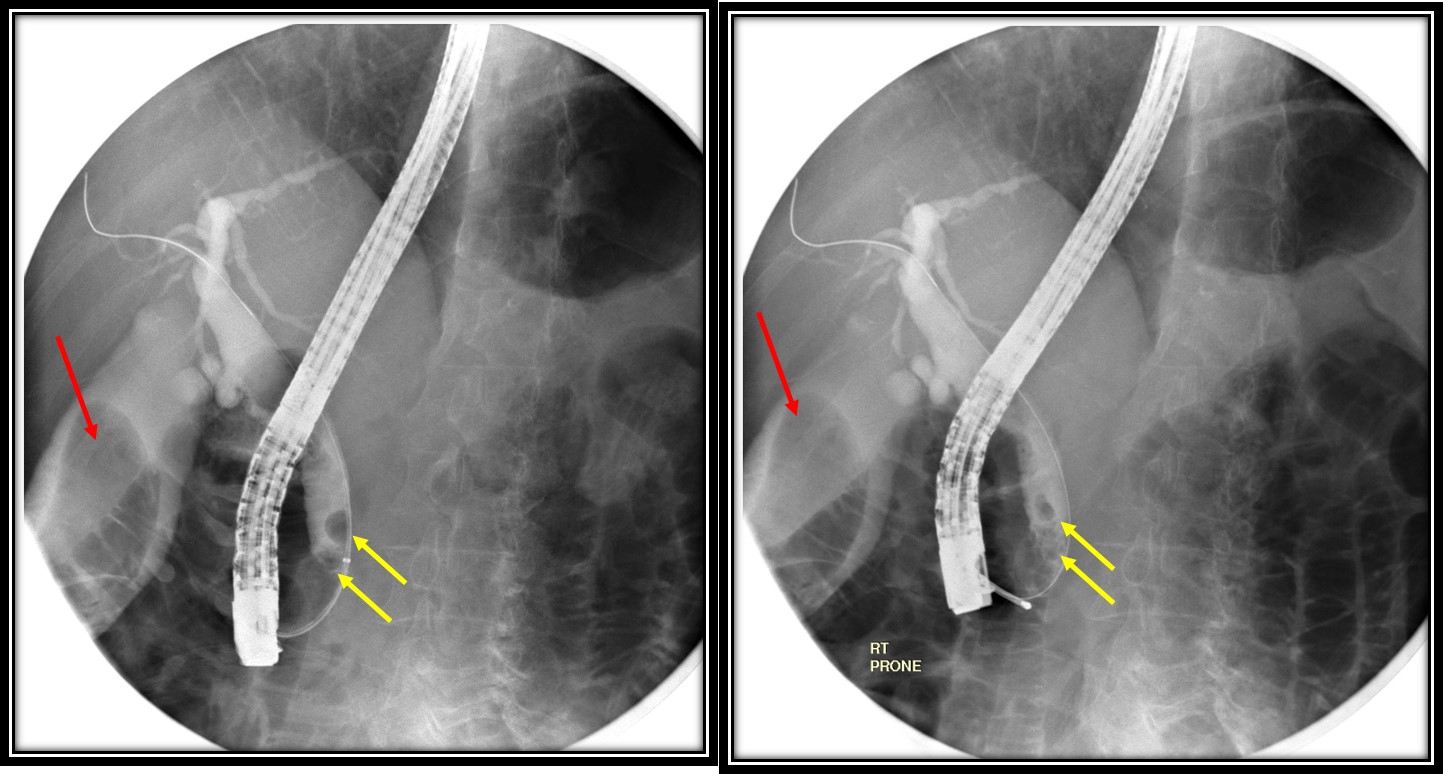

From radiologycases.my

Endoscopic removal of choledocholithiasis Radiology Cases Endoscopic Imaging Findings This is done using a small. Upper gastrointestinal (gi) endoscopy (esophagogastroduodenoscopy [egd]) includes visualization of the oropharynx,. Here, we detail normal and pathologic endoscopic findings in a variety of disease states that are often. An upper gi endoscopy allows an endoscopist to look inside the upper part of your digestive system. An endoscopy is a test to look inside your. Endoscopic Imaging Findings.